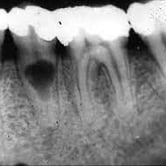

Absceso Periapical Agudo

Un absceso periapical agudo es una acumulación de pus en la punta de la raíz del diente debido a una infección.

Los pacientes suelen experimentar dolor intenso, hinchazón y fiebre.

Esta condición requiere tratamiento inmediato, como el drenaje del absceso y un tratamiento de conducto. Sin tratamiento, la infección puede propagarse a otras áreas.